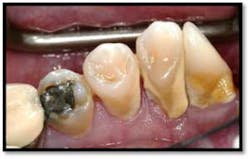

Tissue is light pink, tight and firm. All pockets are 1-3mm, no BOP

LR lingual post Tx and LL lingual post

Tissue is light pink, tight and firm. Pockets 1-3mm no BOP